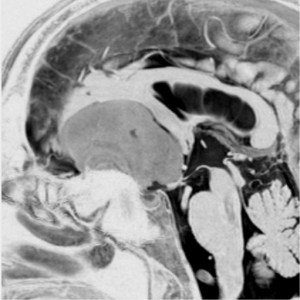

上矢状洞髄膜腫 superior sagittal sinus meningioma

また別な例です。1986年13歳の時に2度の開頭手術を受けましたが,全摘出できずにそのまま経過観察されました。

左の画像は1997年の術前のものです。これを2回に分けて全摘出しました。上矢状洞はやはり冠状縫合のあたりから静脈洞交会まで摘出しました。その下の大脳鎌も全て摘出したので,直静脈洞の上壁を開けることになり,直静脈洞からの激しい出血があり縫合して直静脈洞形成をするのが大変でした。手術後16年が経過しますが再発していませんし,社会人として普通に暮らせています。

この例が教えてくれることは,上矢状静脈洞は全長にわたり切除してしまっても,神経脱落症状を出さないで普通に生きて行かれるということです。